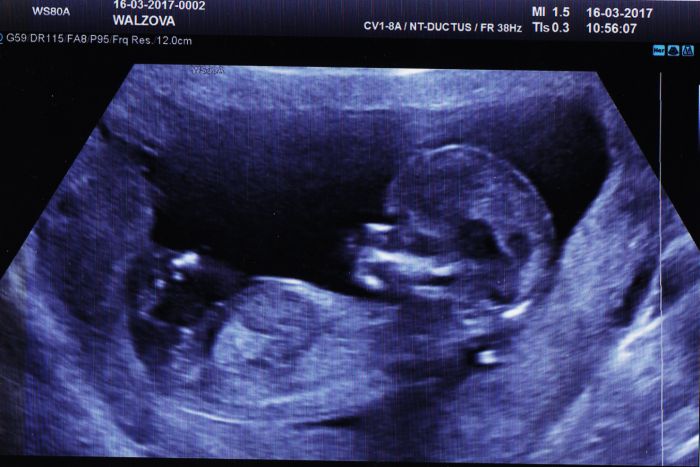

Tak i ja se pridavam s vybornymi vysledky ze screeningu

akorat teda prislo pro me trochu zklamani,ze to bude kluk,chtela jsem druhou holcicku

tak hlavne,ze je to zdravy

Tak dnes jsem byla na screeningu a vyšel NEGATIVNÍ!!!Hurráááá

Čekáme holčičku